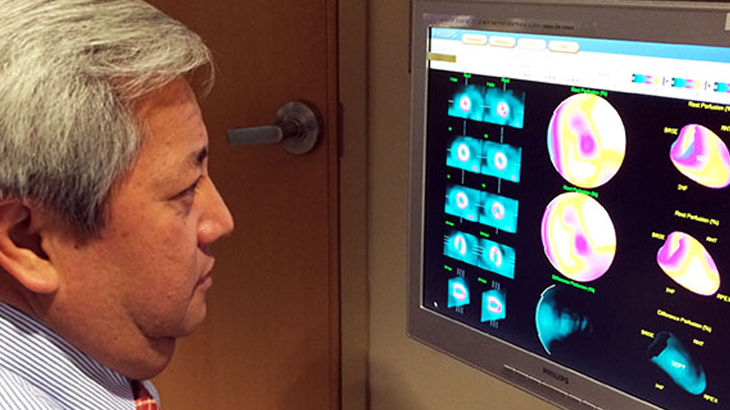

Nuclear cardiology is a branch of nuclear medicine that uses a tiny amount of radioactive material (radioactive tracer) to study the heart. Pictures taken with the radioactive material and a special camera will show both blood flow to the heart muscle and its pumping function.

Gated perfusion imaging evaluates motion of the heart muscle and how well the heart is pumping, which is measured as percent LVEF (left ventricular ejection fraction). This is performed at the same time as myocardial perfusion imaging using a special computer program. Therefore, both blood flow and pumping function of the heart are evaluated in one study and, in the majority of cases, in one visit.

The nuclear medicine division has acquired a new SPECT camera called D-SPECT (Dynamic SPECT), an innovative solid state design camera.

- High-quality images due to twice the imaging resolution of the current conventional SPECT cameras.